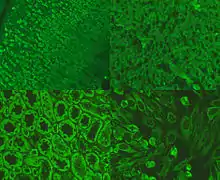

Picture of immunofluorescence staining pattern of AMA antibodies.

Immunofluorescence staining pattern of AMA shown on stomach (top left), liver (top right), kidney (bottom left) and hep-20-10 cells (bottom right).